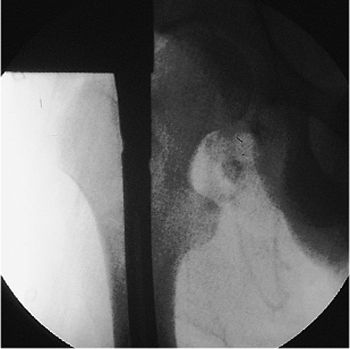

closed right-femur fracture as a result of a head-on motor vehicle

accident. The patient lost consciousness at the site of the accident

and experienced mild retrograde amnesia. On initial examination, the

physician found an obvious, closed, right, midshaft-femur deformity.

The peripheral pulses were intact, and the neurologic examination

showed no abnormalities. Cervical spine, chest, and pelvic radiographs

were normal. A cranial computed tomography (CT) scan was negative for

fracture or intracranial bleed. AP and lateral radiographs of the femur

showed a mid-diaphyseal transverse fracture (see Fig. 21.2). The patient

had an abdominal injury that required exploratory laparotomy. At

surgery, the patient was found to have a complete jejunal transection,

which was subsequently repaired. Immediately after the laparotomy, a

closed intramedullary nailing was performed with a static locked nail.

Because the fracture was mid-diaphyseal, a single distal screw was used

for fixation (Fig. 21.55).

The patient was mobilized on the second postoperative day. The fracture

healed uneventfully in 4 months with excellent restoration of function.

Figure 21.55. Postoperative radiograph.